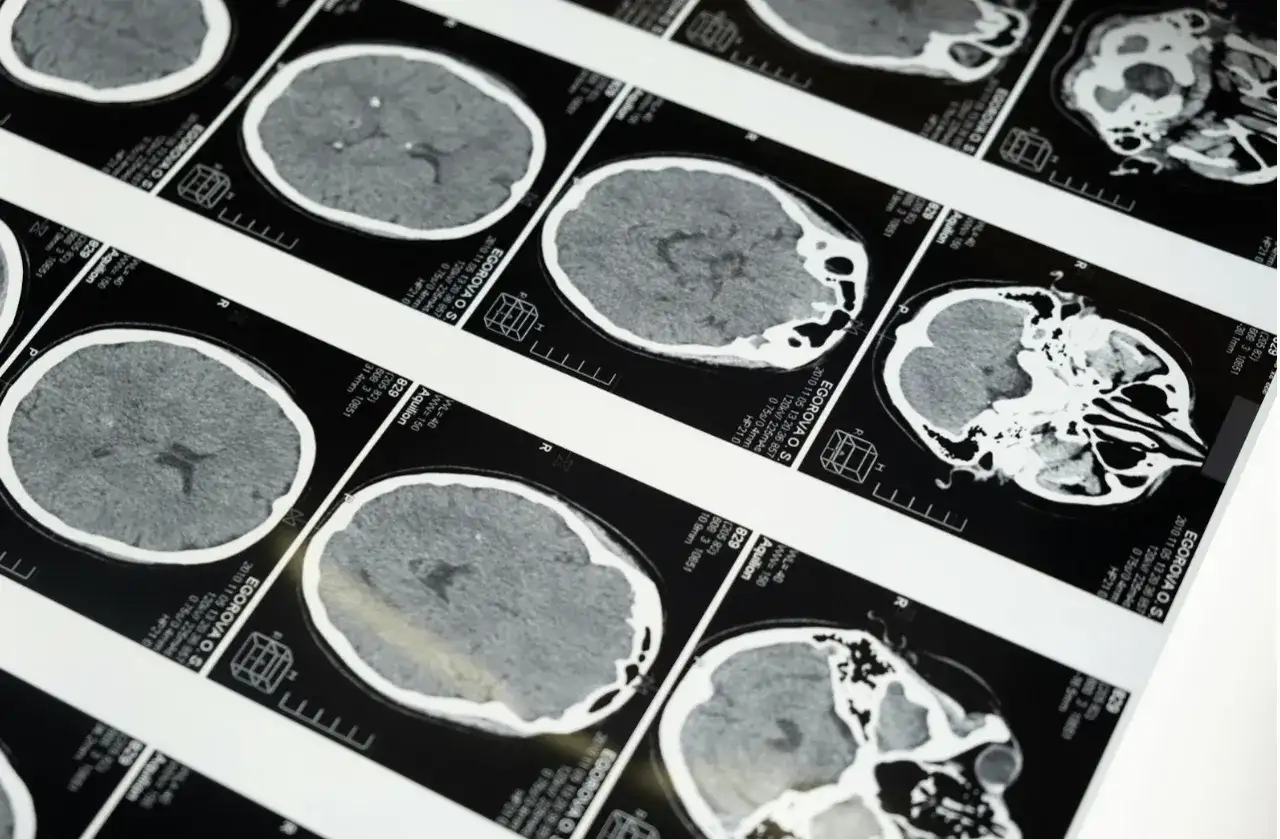

Na czym to polega w praktyce? Badanie wykonujesz lokalnie – RTG, TK, MRI, USG z archiwizacją – a obrazy w formacie DICOM trafiają do zabezpieczonego systemu PACS. Dalej zaczyna się automatyka: system RIS tworzy zlecenie, dołącza dane pacjenta, czasem również krótką informację kliniczną, a całość – zaszyfrowanym łączem – leci do zespołu radiologów. Po drugiej stronie ktoś pracuje w pełnoprawnej stacji diagnostycznej, z medycznym monitorem, kalibracją, narzędziami do rekonstrukcji 3D, MPR/MIP, pomiarów. Nie jest to „oglądanie zdjęcia w e-mailu”, tylko pełen proces diagnostyczny, tyle że zdalny.

- Opis – radiolog otwiera badanie w stacji diagnostycznej, porównuje z wcześniejszymi badaniami, korzysta z szablonów i rozpoznawania mowy.